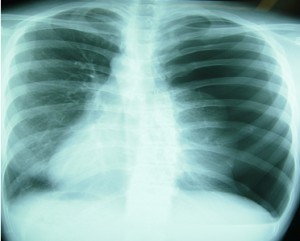

レントゲン例を『気になる病気と症状辞典』さんのサイトからお借りしました。

黒い部分が空気です。

これを見ると、向かって右側にある肺がちっちゃくなり、

その周りの胸腔が空気でいっぱいになってるのが分かりますか?

さらに、その空気に押されて気管が向かって左側に斜めにシフトしています。

そして、向かって左側の肺と心臓(向かって左下の白い部分)が、

これまた溜まった空気に押し寄せられてるのが分かります。

向かって右側の横隔膜も空気に押され通常の状態より下に押されて沈んでいます。